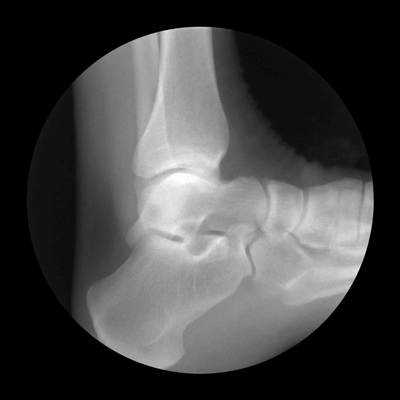

Ankle